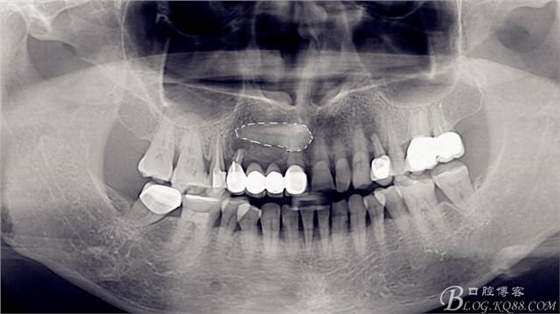

術(shù)前

全景片,此時(shí)此刻已經(jīng)拔除了A4,搔刮牙槽窩去除了囊腫。